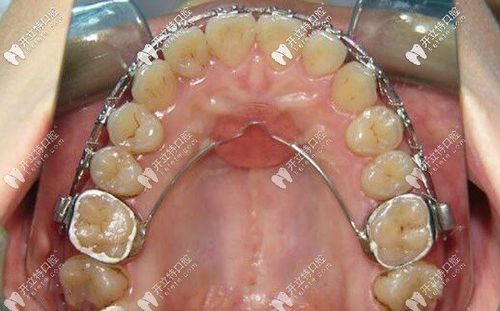

典型病例中,nance弓的应用效果可通过直观图片呈现:一位II类1分类患者拔除上颌第一前磨牙后,佩戴nance弓6个月,通过治疗前后对比可见,上颌第一磨牙无明显近中移动(磨牙间距保持稳定),而拔牙间隙内收整齐,腭托与腭部贴合良好,无黏膜刺激,图片中清晰的磨牙位置变化与腭托状态,直接反映了nance弓的支抗控制效果。

- 带环粘接:选择合适尺寸的磨牙带环,试戴后用玻璃离子水门汀粘接,图片可显示带环在磨牙上的位置(需位于龈上1-2mm,避免压迫牙龈),以及颊面管的朝向(应与牙长轴平行,便于弓丝插入)。

- 粘接与调整:将腭托与弓丝整体粘接,检查磨牙有无移位,咬合是否干扰,术后拍摄X线片或口内照片,确认装置位置正确(腭托位于腭穹顶前部,与黏膜无间隙),为后续治疗提供基线资料。